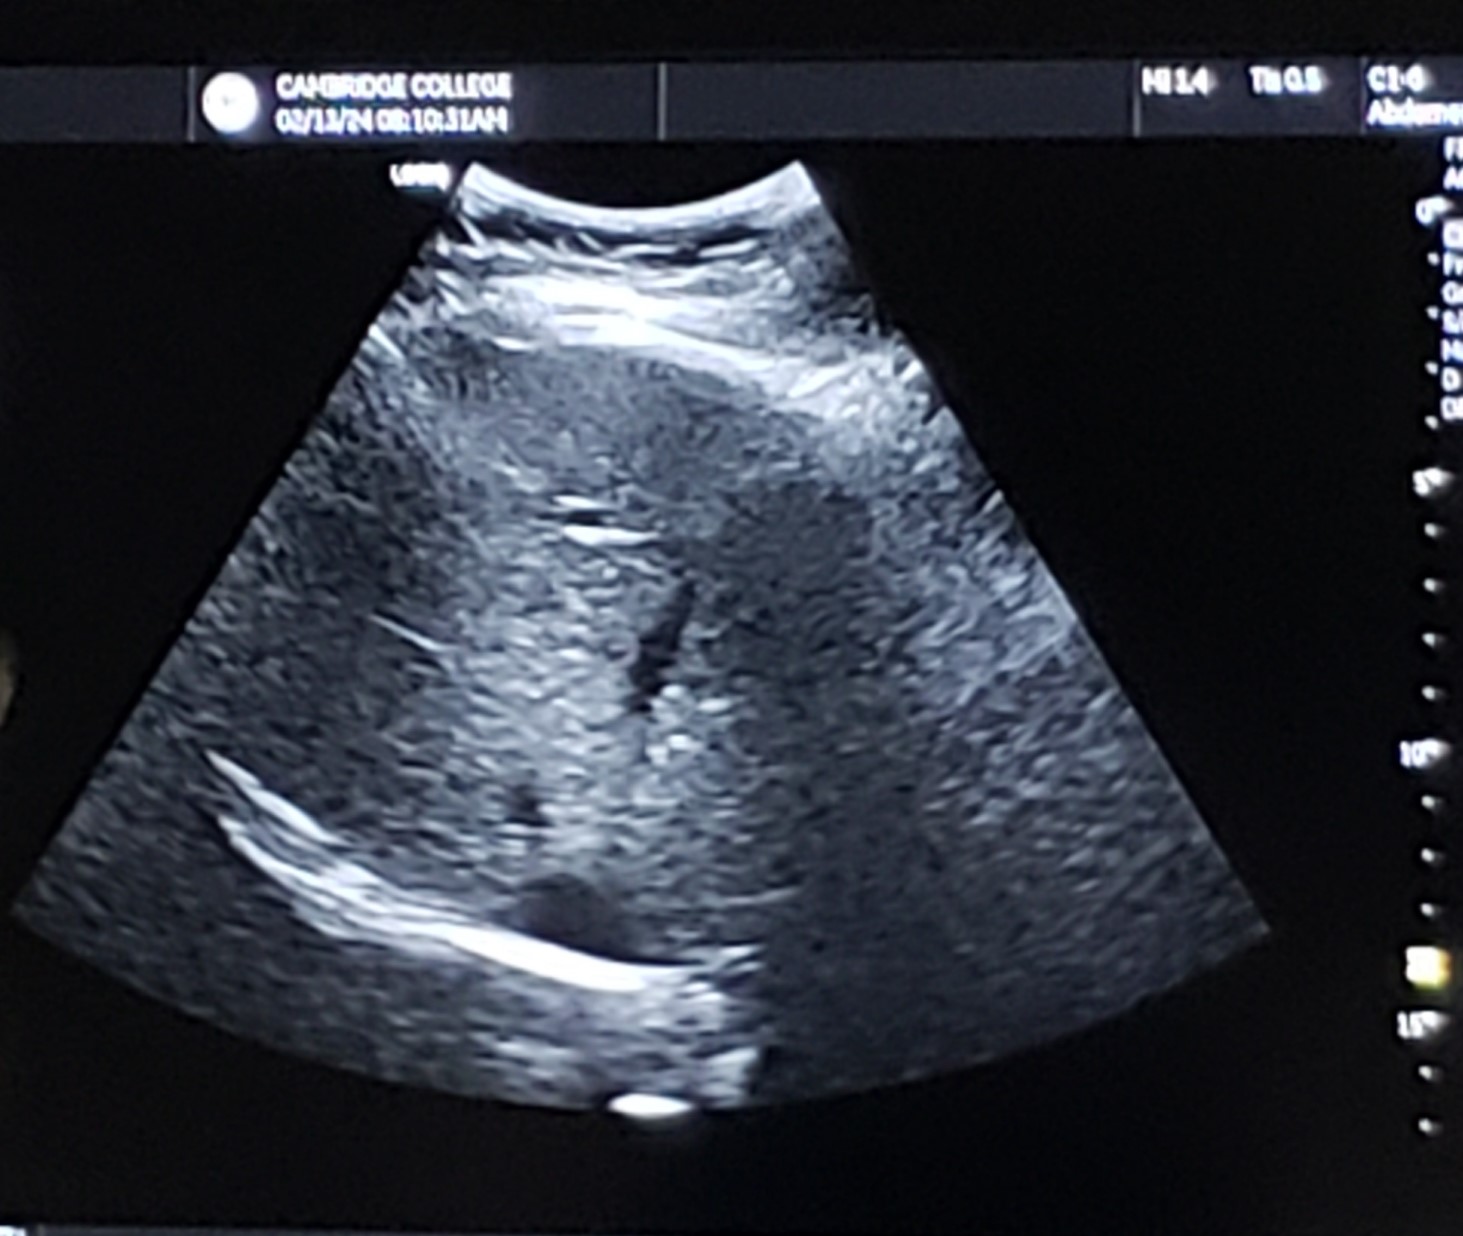

Trans RLL dome (w/ visible Hepatics if possible)

13